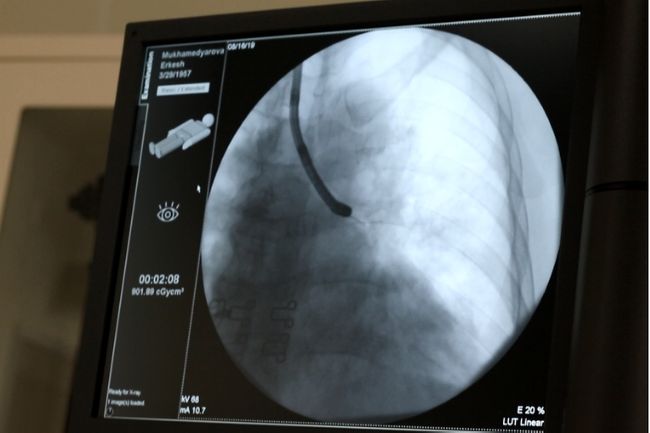

А теперь представьте себя в операционной: с помощью эндоскопа продвигаемся через просветы бронхов - сквозь трубку диаметром 6 миллиметров проводим еще более тонкие иглы для выполнения манипуляции в легком и в лимфоузлах. При этом поле нашего действия (сегмент легкого, пределы предполагаемого образования) мы перед этим подробно изучили благодаря снимку компьютерной томографии пациента, потому знаем, в какой области нам необходимо действовать. Но для точности этого недостаточно: навигатором во время самой манипуляции нам служит рентген - по нему мы видим, как и в каком направлении движутся наши инструменты в самом легком в режиме "прямого эфира": на экране мы видим картину легкого, благодаря которой управляем всем процессом изнутри.